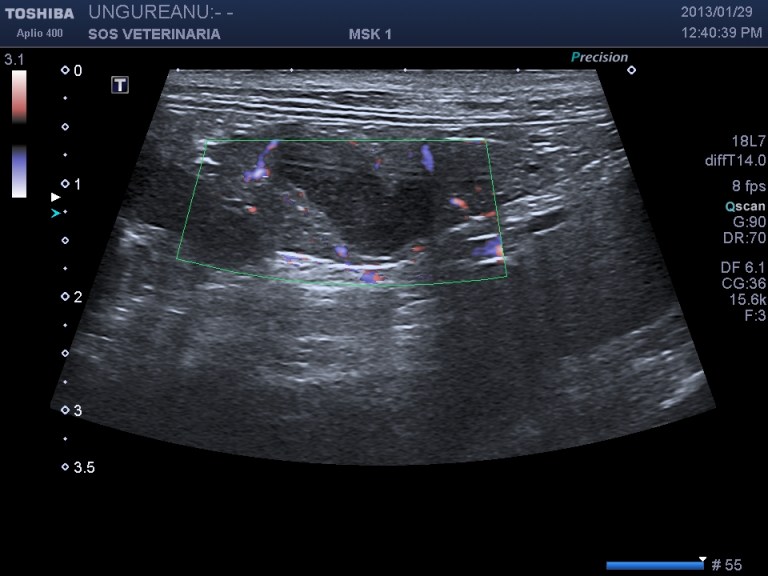

evidente la dilatazione e l’ispessimento   della parete  a carico di coleciste e coledoco con   formazione presfinterica di un ampolla ectasica simil diverticolo probabilemente secondaria alla cronicita’ del processo ,non si evidenziano ostacoli calcolotici o neoformazioni occludenti  il deflusso intra o extraluminali e a livello della papilla , il pancreas si presenta omogeneo ipoecogeno iperplastico trama vasale  ben evidenziabile .

Una  terapia di lunga durata con prednisolone alla dose di 0,5 mg/Kg sid comninata con marbofloxacillina e metronidazolo ha portato  dopo 4 settimane a risoluzione clinica e di laboratorio e ad un notevole miglioramento dell’imaging ,permane a distanza di 2 mesi  l’ectasia del dotto pancreatico e mofificazioni preampollari del coledoco con grado di distensione molto ridotto. Si e’ concluso  per un processo infiammatorio  possibile complesso colagioepatie ibd pancreatite (triatide)  con fenomeni iperplastici e fibrotici  a livello della papilla duodenale  e stenosi parziale del deflusso intraparietale duodenale ,tuttavia l’assenza di esami istopatologici non permette conclusioni certe eziopatogenetiche se non le evidenze riscontrate durante il decorso. Dopo due mesi il paziente alla sospensione dei farmaci mantiene la remissione.

DOPO 4 SETTIMANE DI TERAPIA ANTIBIOTICA E CORTICOSTEROIDEA